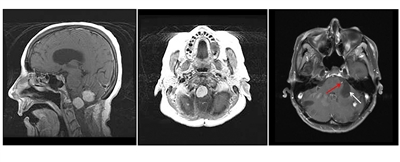

Hemangioblastomas are the most common disease manifestation in patients with VHL, affecting more than 70% of individuals. A prospective study assessed the natural history of hemangioblastomas.[16] The mean age at onset of central nervous system (CNS) hemangioblastomas is 29.1 years (range, 7–73 y).[17] CNS hemangioblastomas were most commonly seen in the cerebellum (45%), spinal cord (36%), cauda equina (11%), and brain stem (7%).[18] While sporadic hemangioblastomas are generally solitary in nature, the VHL-associated CNS lesions are often multifocal. After a mean follow-up of 7 years, 72% of the 225 patients studied developed new lesions.[18] Figures 2 and 3 depict cerebellar and spinal hemangioblastomas, respectively, in patients with VHL.

Three-panel image showing a sagittal view of two prominent light-colored brainstem and cerebellar lesions (left panel), an axial view of a prominent brainstem lesion (middle panel), and an axial view of a cerebellar lesion with a large, dark area that is a cystic component (right panel).

Figure 2. Hemangioblastomas are the most common disease manifestation in patients with von Hippel-Lindau disease. The left panel shows a sagittal view of brainstem and cerebellar lesions. The middle panel shows an axial view of a brainstem lesion. The right panel shows a cerebellar lesion (red arrow) with a dominant cystic component (white arrow).